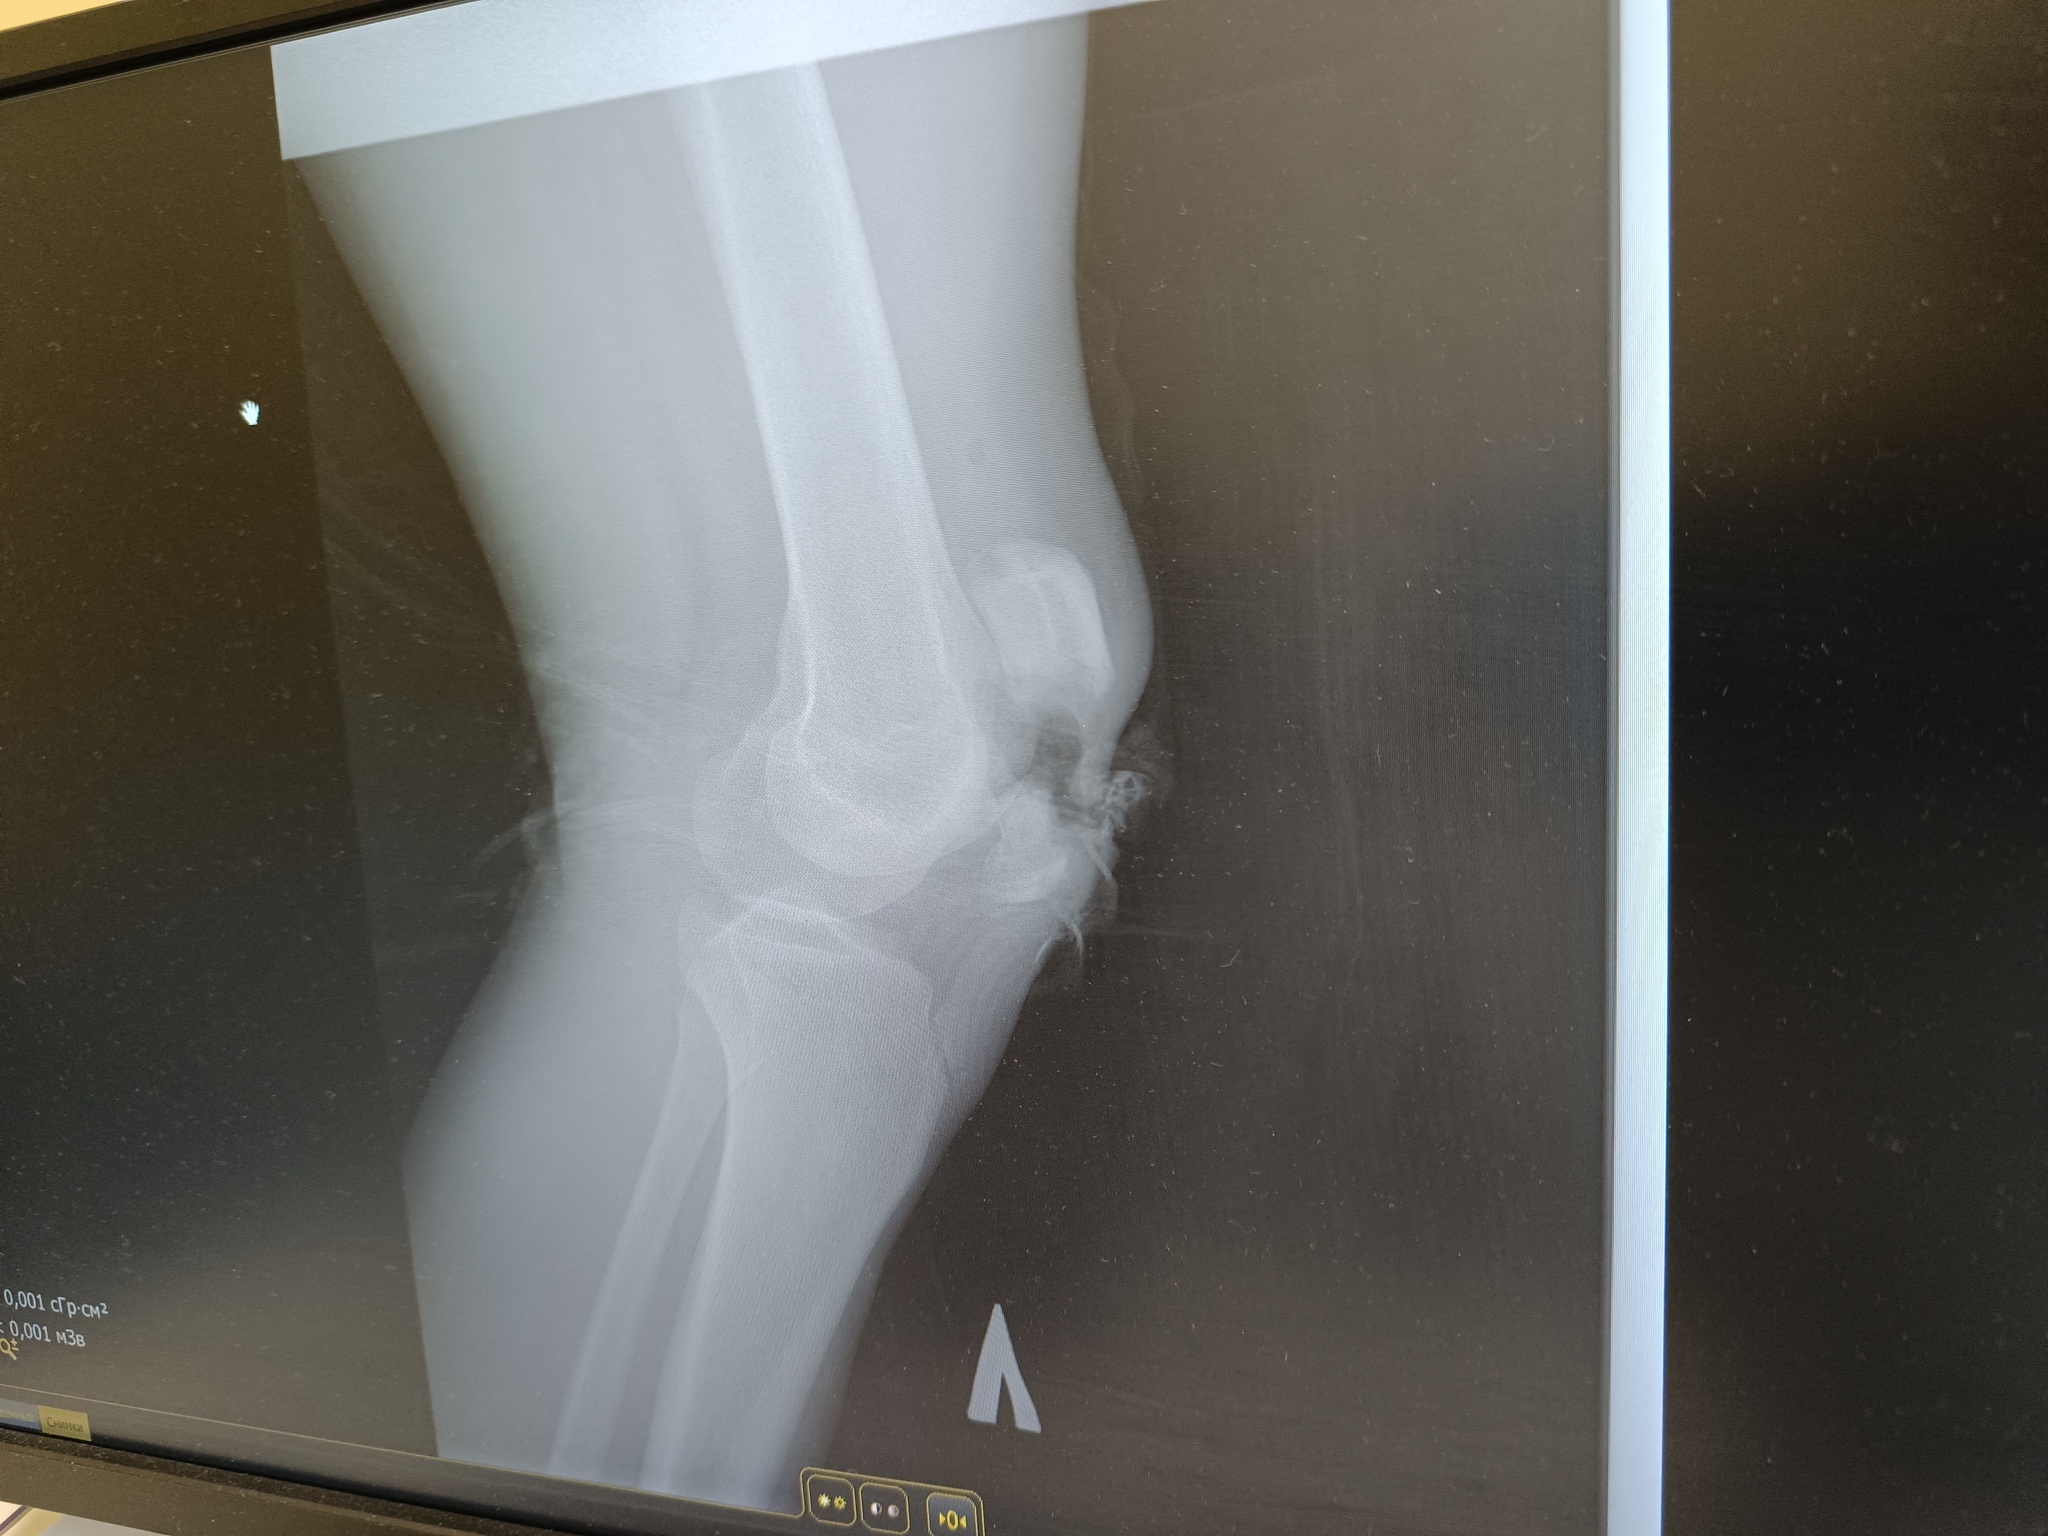

Похожая была история ) только открытый перелом )

Иллюстрация к комментарию